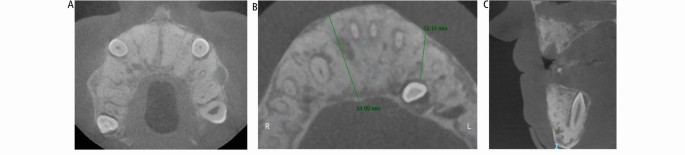

Figure 3 and Figure 4 show the radiographic appearance and CBCT of the jaws, confirming the bony appearance and expansion.

Case 1: cone-beam computed tomography scan. (A, B) Axial views of the maxilla and mandible showing the bone expansion and the position of the impacted canine teeth. (C) Sagittal view of the anterior maxilla and mandible showing the bone expansion and the position of the impacted canine tooth